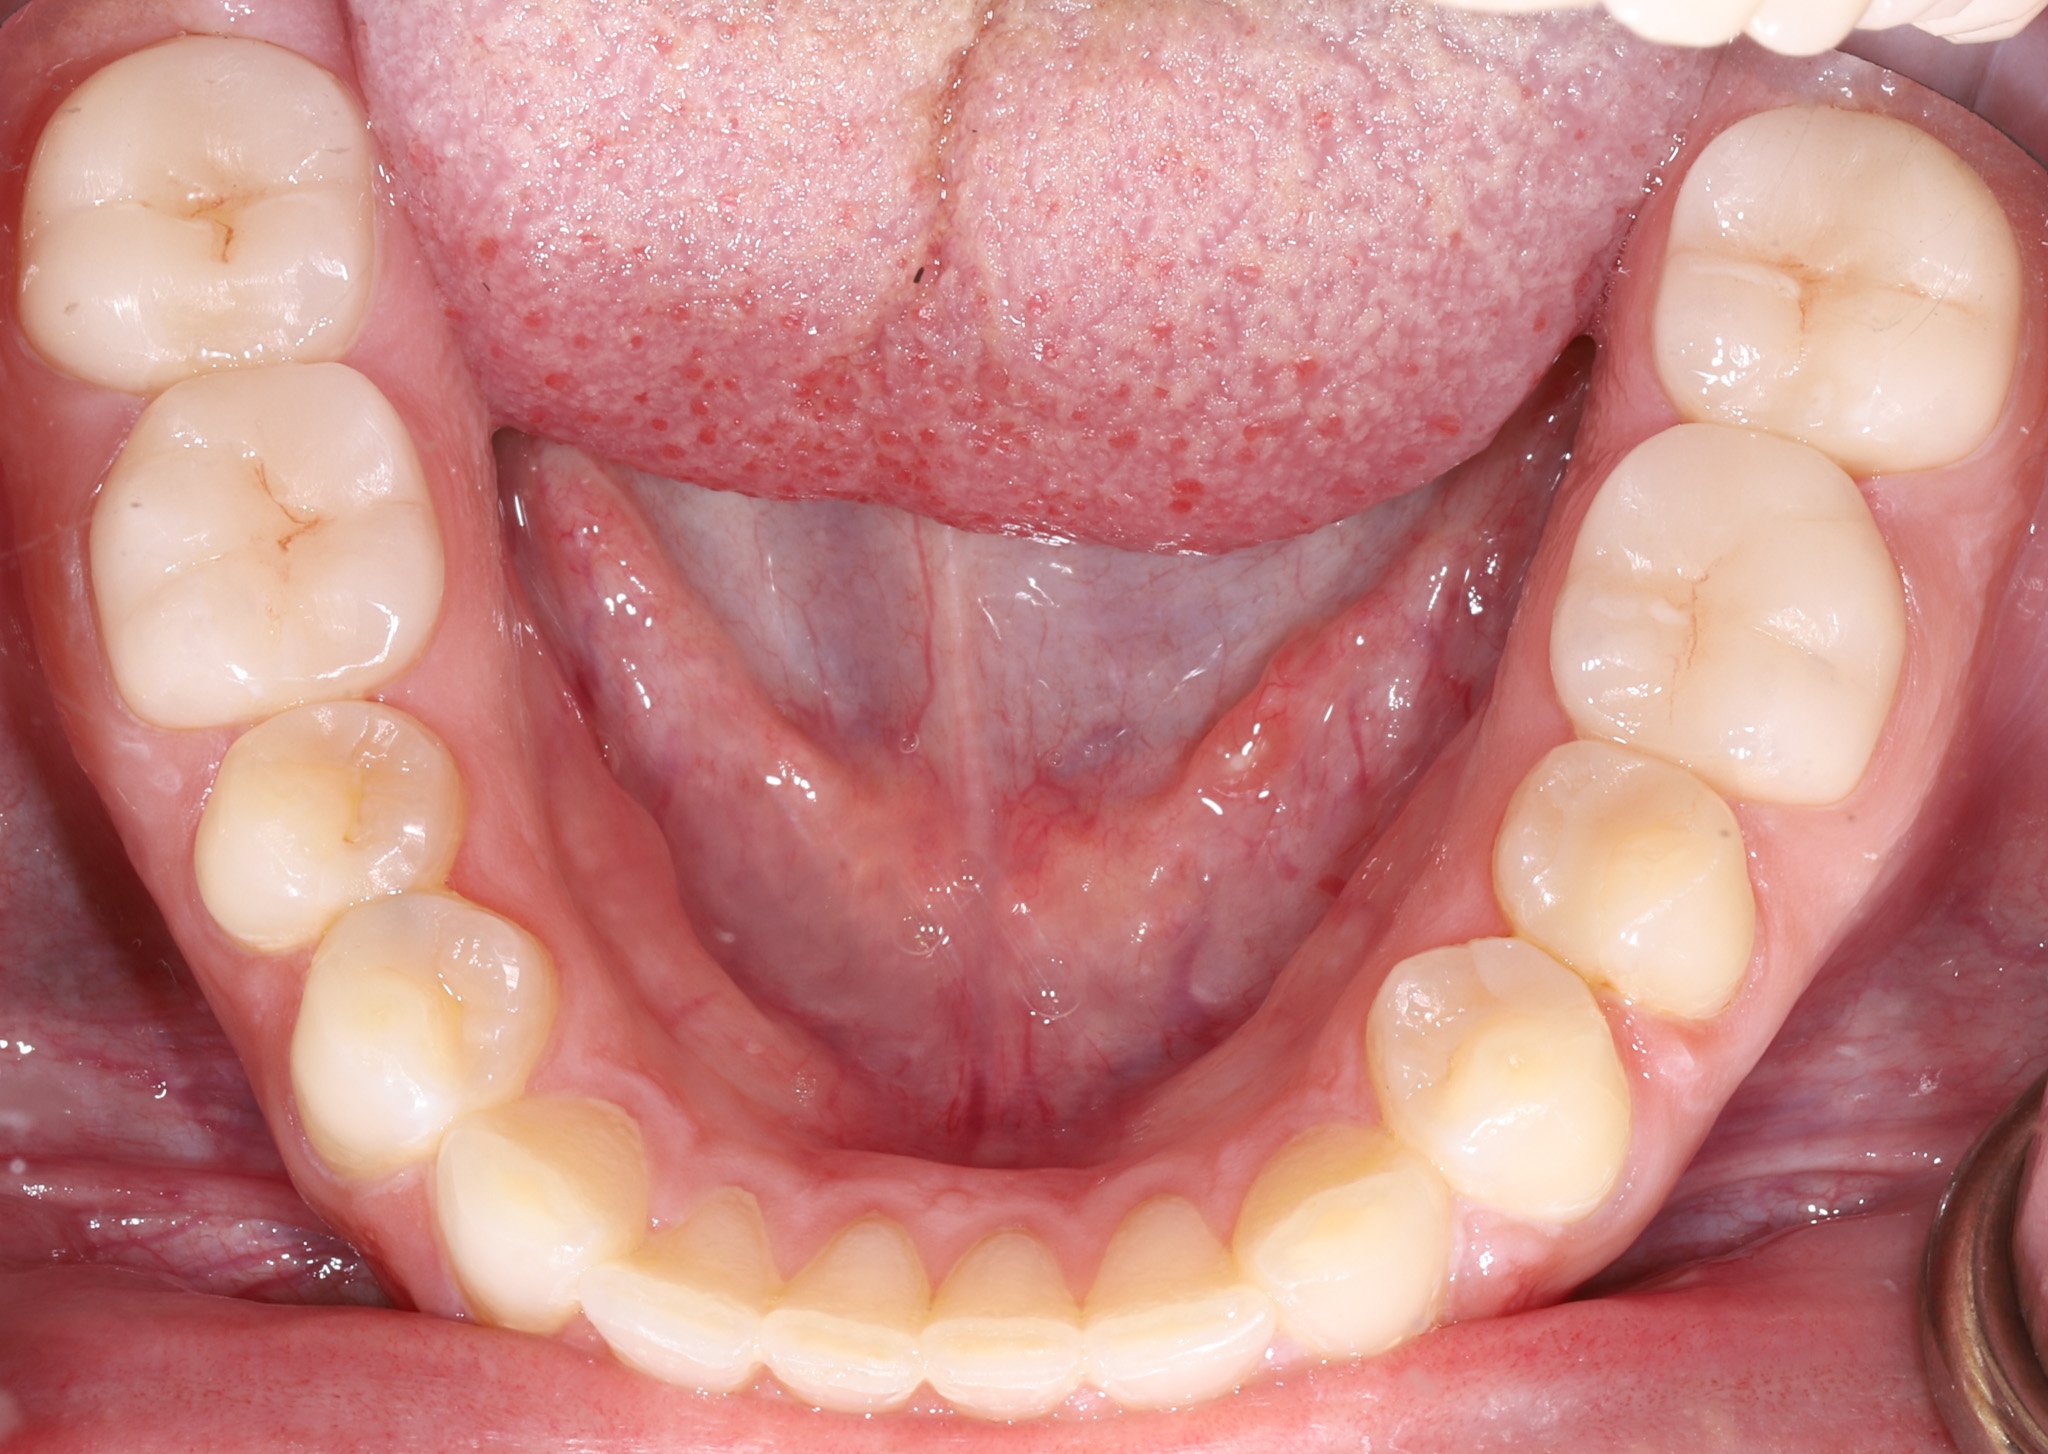

A patient's teeth with old, failing dentistry. Prior to restoring.

Before: Old dentistry that doesn’t fit, decay, acid erosion

A patient's teeth after restoring with bonded porcelain and gold restorations.

After: Bonded porcelain and gold restorations to restore what was lost